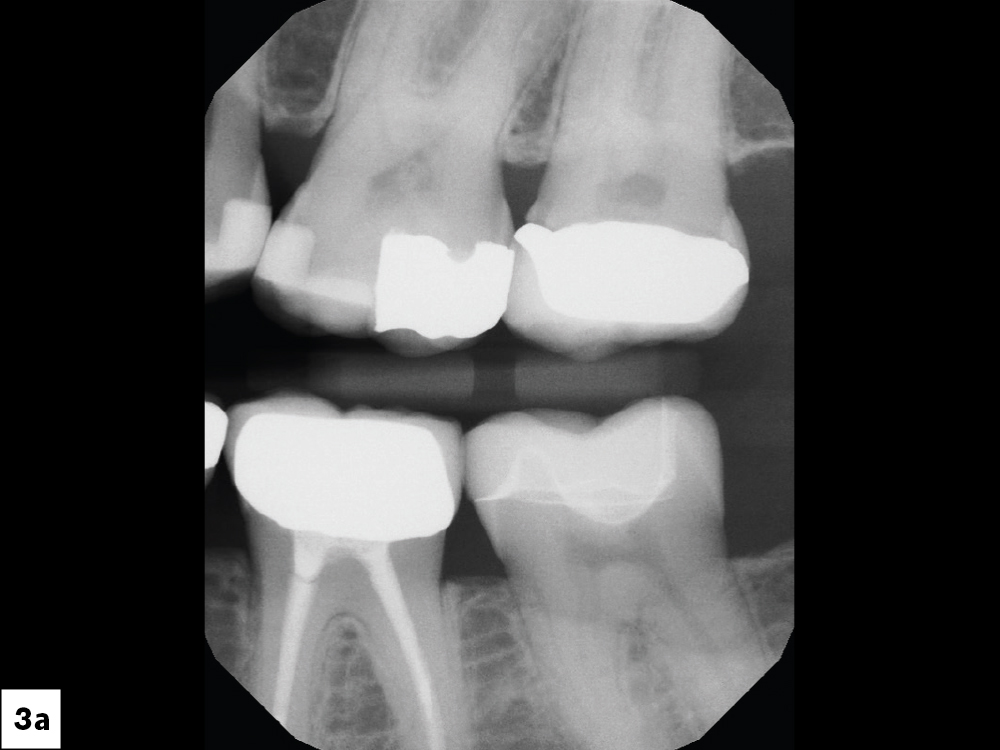

Radiographs verified the open margin

Figures 3a, 3b: Radiographs verified the open margin, and the treatment plan called for restoration of the tooth with a same-day BruxZir® Esthetic NOW Posterior crown.